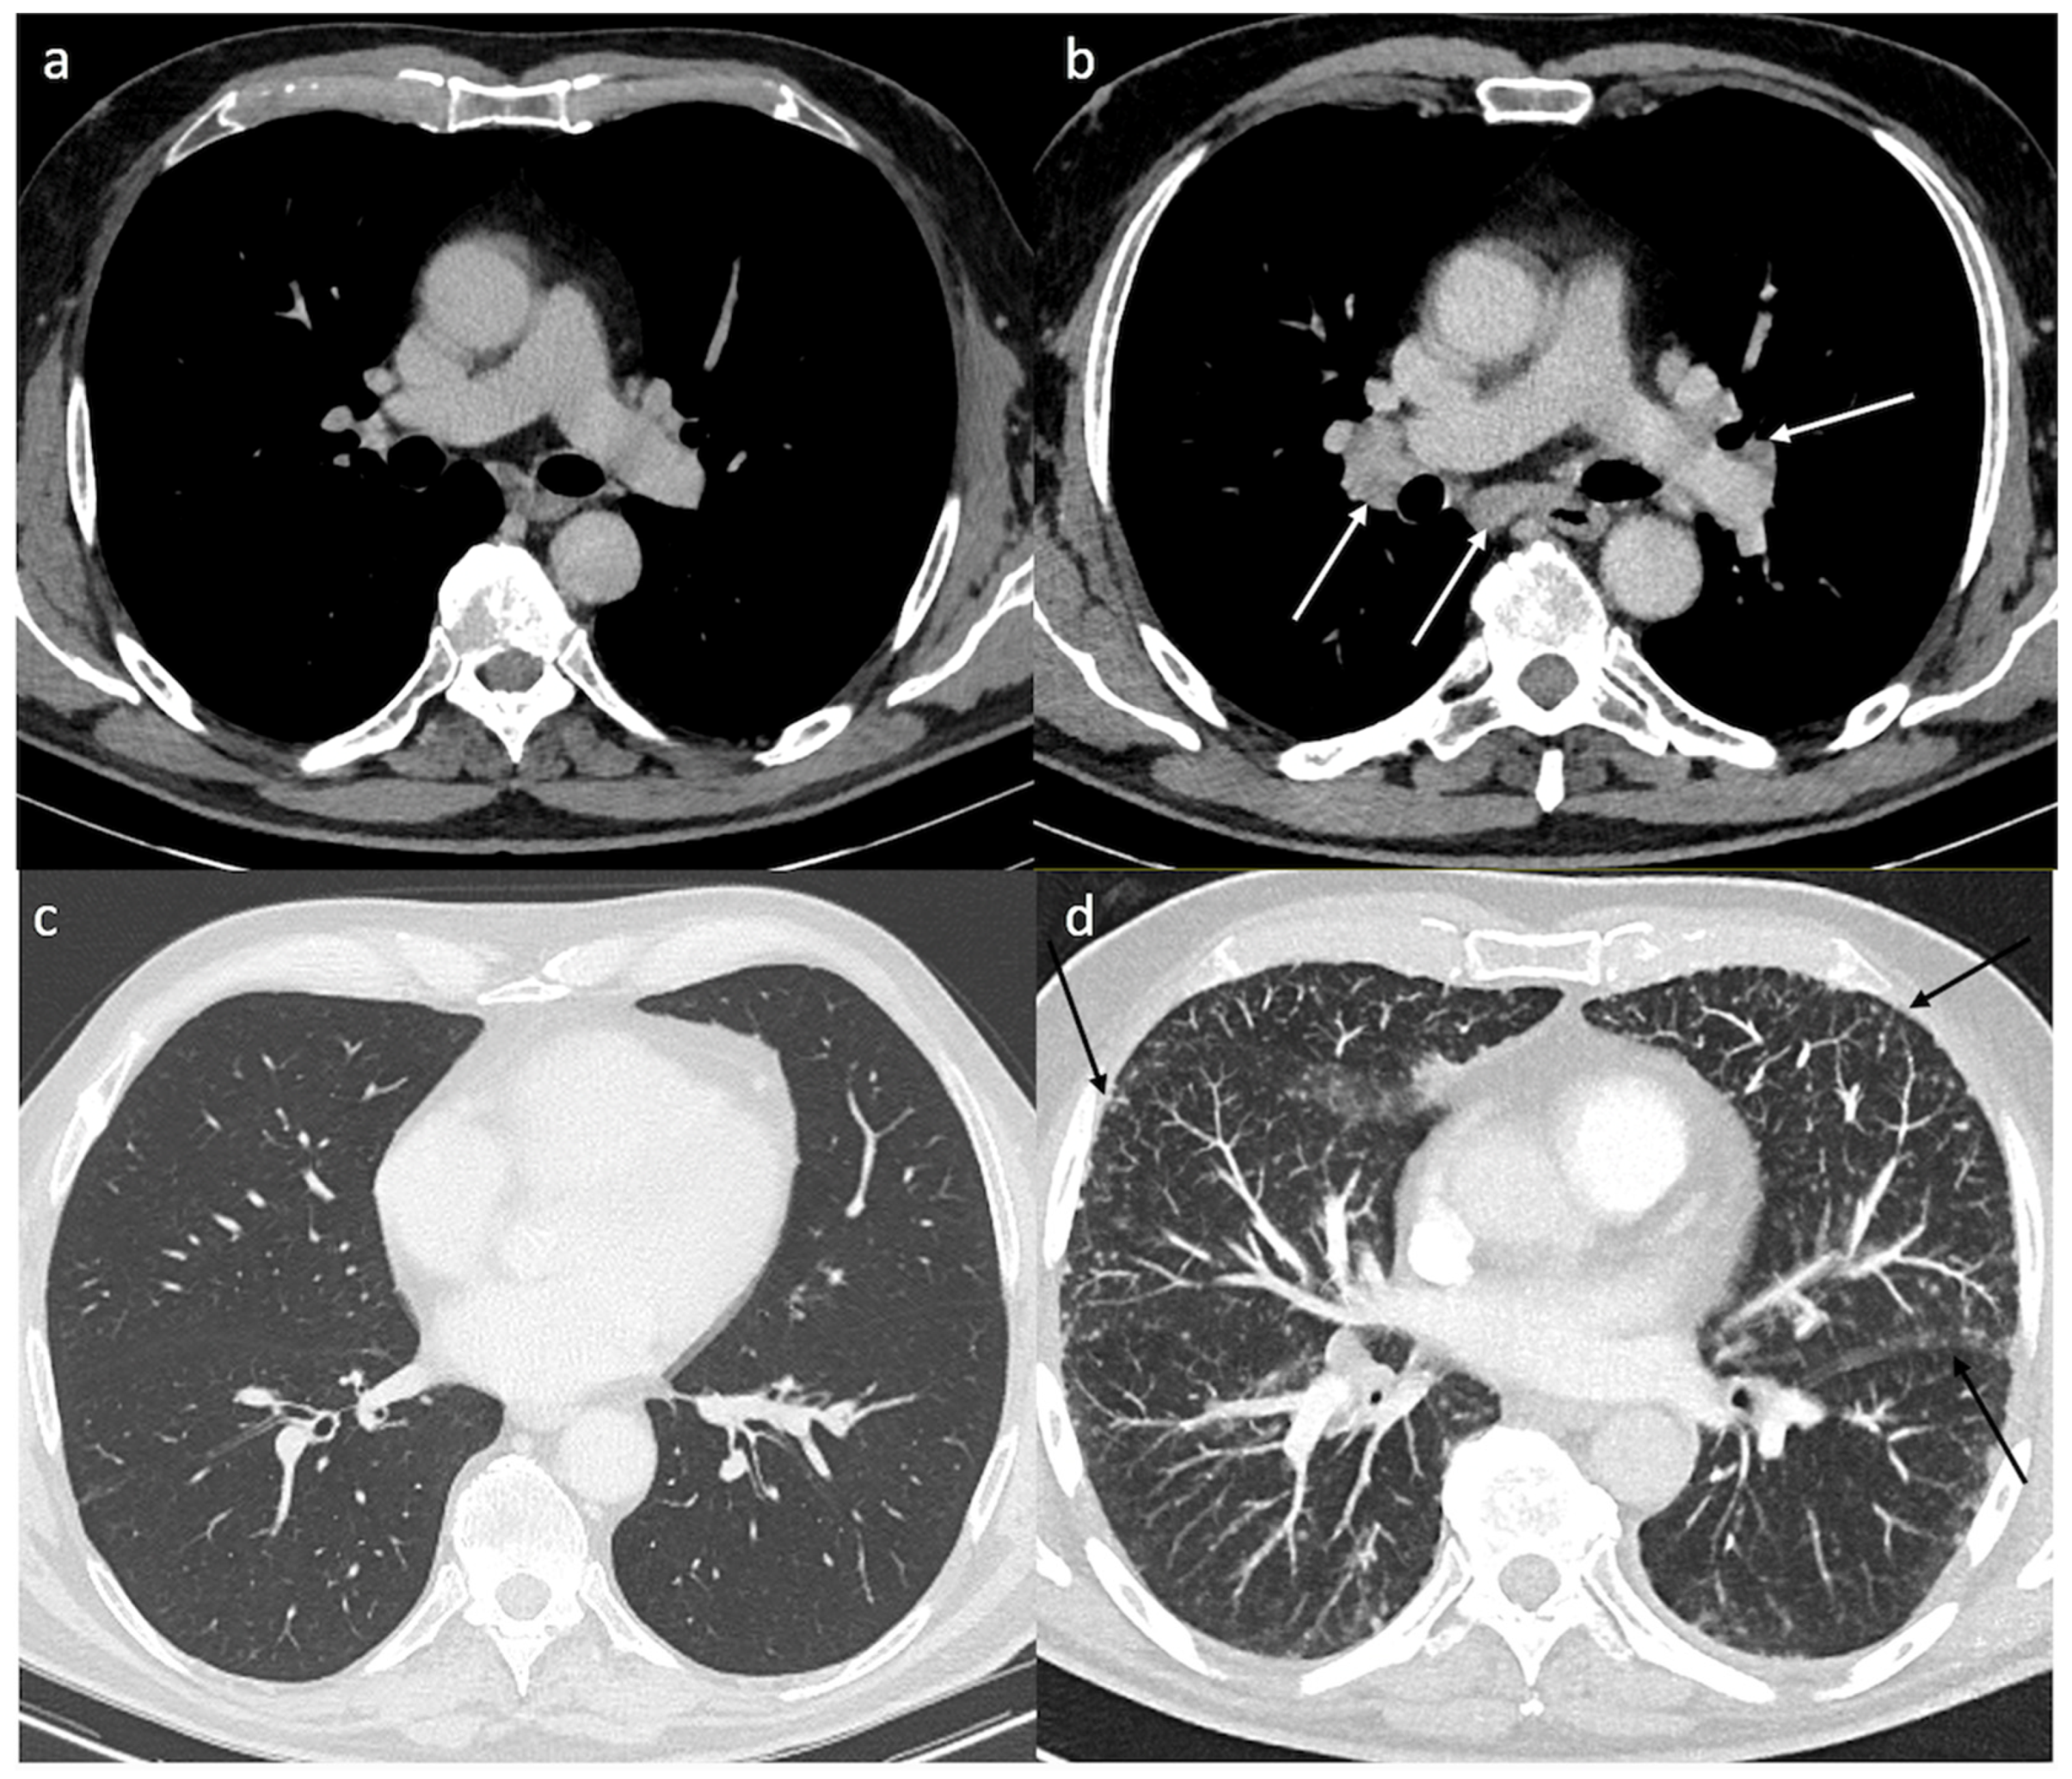

3. Results